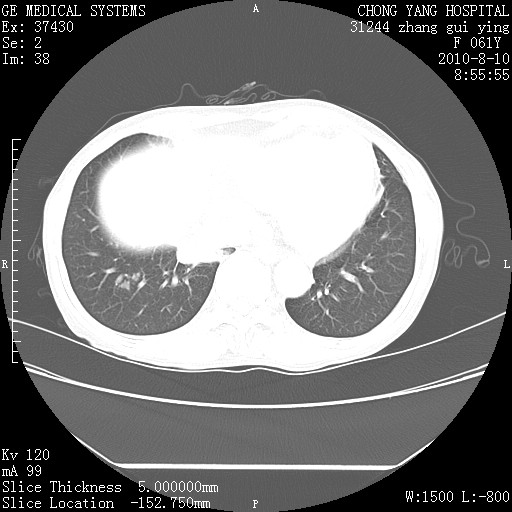

标题: CT28314:F61Y胸部增强,发热咳嗽一周入院,后面的为一周前平 [打印本页]

标题: CT28314:F61Y胸部增强,发热咳嗽一周入院,后面的为一周前平

右肺下叶中心性肺癌可能性大

1、支持考虑右侧中央型肺癌伴右肺中叶节段性不张及下叶支气管黏液痰栓    2、左肺上叶舌段感染。

支持右下肺中央型肺癌并左上肺感染.

我也觉得右肺中叶支气管受累

双肺感染性病变,不除外合并结核感染。

支持3楼意见,还要考虑:纵隔及肺门淋巴结转移、右侧少量胸腔积液。

支持考虑右侧中央型肺癌

确切的说:1:右肺下叶中心型肺癌侵及中叶支气管并中叶不张,纵膈淋巴结转移。2:左肺舌叶炎症。3:右侧胸腔少量积液

块影平扫32hu,动静脉期62-70hu.

1:右肺下叶中心型肺癌侵及中叶支气管并中叶不张,纵膈淋巴结转移。2:左肺舌叶炎症。3:右侧胸腔少量积液。支持!

右肺下叶内基底段近膈不规则肿块,考虑右肺下叶周围型肺癌可能性大。

考虑右下肺肺癌,纵隔淋巴结转移i。

右肺下叶中心型肺癌侵及中叶支气管并中叶不张,纵膈淋巴结转移。2:左肺舌叶炎症。3:右侧胸腔少量积液